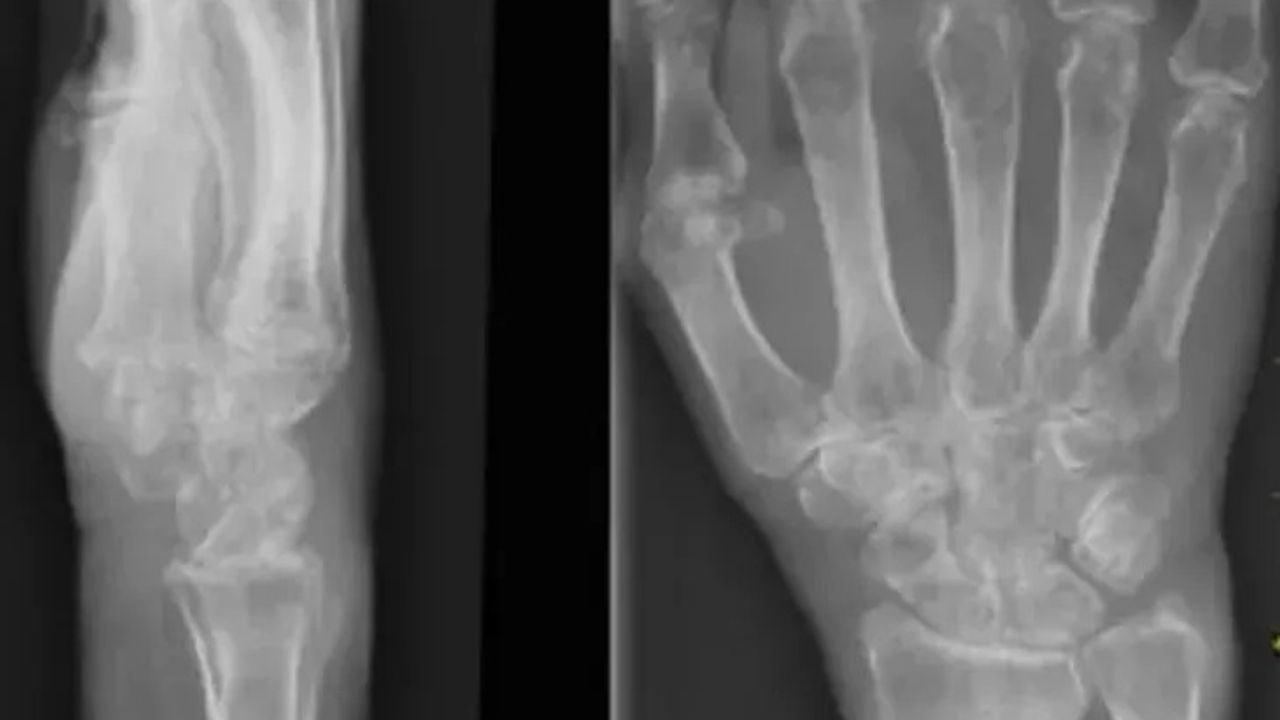

Erken menopoz, ailede kalça kırığı öyküsü, uzun süreli kortizon kullanımı ve tütün-alkol tüketiminin riskleri artırdığını vurgulayan Yeşil, hastalığın en ağır sonuçlarının kalça kırığı ve omurga çökmesi olduğunu ifade etti. Yapılan araştırmalara göre kalça kırığı yaşayan bireylerin iki yıl içinde yüzde 12 ile 20 arasında ölüm riski taşıdığını belirten Yeşil, bu durumun yaşam konforunu tamamen yok ederek, kişiyi başkasına bağımlı hale getirdiğini ekledi.

Osteoporozun sessiz ilerleyen ancak önlenilebilir bir hastalık olduğunu sözlerine ekleyen Yeşil, "Geleceğimiz için vücudumuza yatırım yapmalıyız. Bunu beslenme, egzersiz ve düzenli takiple sağlayabiliriz" diye konuştu.